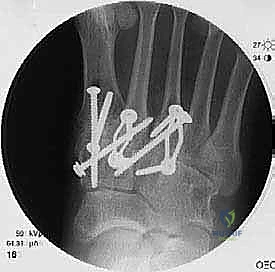

6. التثبيت الصلب (Rigid Fixation)

لضمان التحام العظام لتصبح عظمة واحدة صلبة، يجب تثبيتها بقوة هائلة حتى لا تتحرك أثناء فترة الشفاء. يتم استخدام مسامير معدنية متطورة (Screws)، أو شرائح معدنية خاصة (Plates)، أو دبابيس طبية متخصصة (Staples) مصنوعة من التيتانيوم الآمن على الجسم.

7. الإغلاق والضماد

بعد التأكد التام من وضع العظام وثباتها باستخدام جهاز الأشعة السينية داخل غرفة العمليات (C-Arm)، يتم إغلاق الشقوق الج